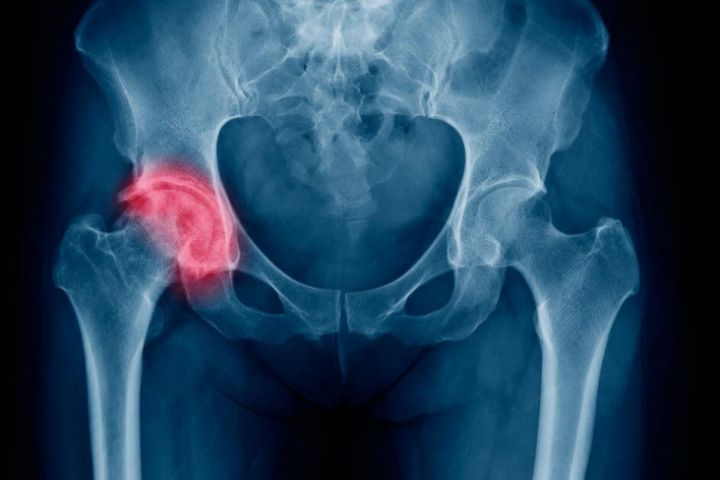

Переломы шейки бедренной кости

Экстренная и плановая помощь при переломе шейки бедренной кости в ГКБ им. А.К. Ерамишанцева